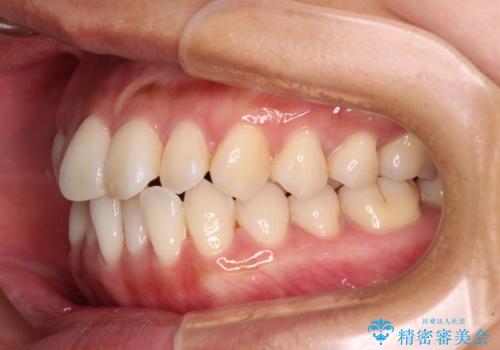

- 前歯のデコボコで前方に出ていることを気にして来院された患者様です。

上顎前歯が捻れて前方に飛び出しており、下顎前歯もそれに沿うようにデコボコとなっていました。

IPR(歯と歯の間を削る処置)によりスペースを獲得して上下顎前歯のデコボコを改善し、飛び出している前歯が引っ込むように設定し、インビザラインにて矯正治療を行うこととしました。

装着時間を守ってくださったので、予定通りの期間で終えることができました。インビザライン特有の、奥歯の咬み合わせの問題もなく、しっかりと歯列を改善することができました。